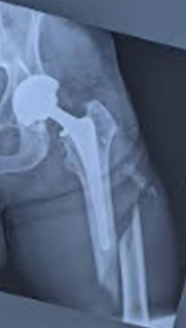

Initial fracture, fixation, and broken hardware